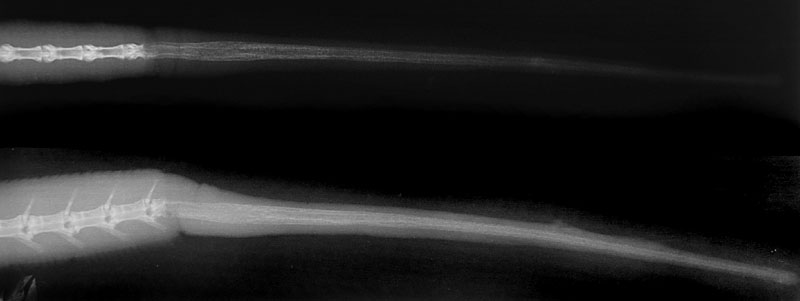

離脱面からが椎骨は再生されませんが、代わりに軟骨の茎が生成され、それが元の尾と同じ長さに近くまで伸長します(軟骨幹)。記録された尾の再生速度は、種類によってかなり異なり、1日あたり0.2~2mmの範囲です〔Arnold 1984,Hughes et al.1959,Jamison 1964〕。しかし、アシナシトカゲの一部の種類では、再生にはかなりの時間を要し、11ヵ月で4.1mmしか再生しません〔Miller et al.1944〕。尾の再生は種類はもちろん、栄養状態、成長期や繁殖期などの時期にも影響を受けます〔Vitt et al.1977〕。ヤモリでは尾の再生を優先した場合、身体の成長は遅くなり、生体の繁殖を優先した場合は、尾の再生は遅くなります〔Dial et al.1981〕。自切した尾と切断された尾はどちらも同様に再生しますが、アノールトカゲを対象とした研究では、切断された尾は自切した尾に比べて再生尾が短いことが報告されています〔Bellairs et al.1985〕。

周囲の筋肉は均質な層あるいは元の構造を模倣して軟骨茎の周りに放射状に広がりながら再生されます。 動脈と静脈も新しい組織とともに成長します。一部のトカゲでは、軟骨幹の中央に椎管の模倣として、結合組織と血管が詰まっていることがあり、 脊髄からの神経組織の成長の兆候も付随的に観察されています〔Zwart et al.2006〕。元の尾と再生尾の間に構造および機能上の違いがあるため、特に再生尾は、調整された細かい動きがあまりできないと予測されています〔Fisher et al.2012〕。しかしながら、一部のヤモリ科トカゲの再生尾は柔軟性を保っており、元の尾と比べて機能に大きな低下は見られず、これらのトカゲの軟骨基質には多量のエラスチンが含まれているため、再生尾ははるかに多用途に使用できるそうです〔Alibardi et al.1989〕。再生尾の軟骨管には離断面がないため自切することはできず、再自切の際には毎回基部に近い尾椎で行われ〔Bellairs et al.1985,Elwood et al.2012〕、繰り返し尾の切断を経験するトカゲは、尾の付け根に近づくにつれて尾を徐々に短くなります〔Chapple et al.2004〕。

ヒョウモントカゲモドキではX線では軟骨が見えませんが、CT像では硬い構造物が尾の中心部に走行しているのが分かります。再生尾にも次第に脂肪細胞が蓄積して肥大します〔Alibardi 1995〕。